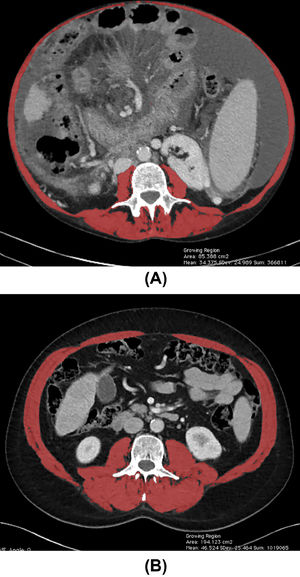

According to AASLD and the FLEXIT (Fitness, Life Enhancement, and Exercise in Liver Transplantation) consortium, skeletal muscle index (SMI) assessed by computed tomography (CT) is the current gold standard to identify sarcopenia among patients with cirrhosis. The FLEXIT consortium defines sarcopenia in patients with cirrhosis by a cut-off value of SMI <50 cm2/m2 in male and <39 cm2/m2 in female patients, respectively, measured in cross-sectional imaging at L3 vertebral level [10,11]. Fig. 2 illustrates total muscle area quantification at L3 vertebral level measured in an abdominal CT.

Total muscle area quantification at the level of the third lumbar vertebra using abdominal CT images from two patients with cirrhosis. (A) Female patients with low SMI (32.21 cm2/m2) and (B), and male patients with high SMI (67.17 cm2/m2), as indicated by the red shading. SMI, skeletal muscle index. (For interpretation of the references to color in this figure legend, the reader is referred to the web version of this article.)